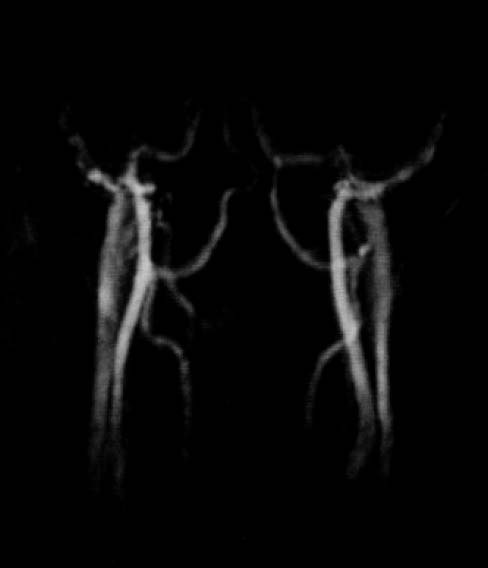

図16.頸部血管の位相コントラスト法MRA.

【要旨】移動するスピンと静止スピンでは勾配磁場を加えたときの位相変化が異なる事を利用して,移動するスピンを選択的に画像化する方法を考案した.位相を利用して,収縮期と拡張期の画像から血流を検出する方法は既に報告されているが,この場合は拍動流しか検出できない.本法は,極性の異なる対称性の勾配磁場,すなわちフローエンコード勾配磁場(flow encoding gradient)を加えて撮像し,これをサブトラクションすることにより,動脈,静脈ともに画像化することができる.フローエンコード勾配磁場は任意の1つあるいは複数の方向に印加できる.

特徴として,バックグラウンドの抑制が非常に良好であること,最大位相シフトが1ラジアン以下の場合,ピクセル輝度と輝度が概ね線形な関係にあるので流速を定量できることがある.ただし,位相シフトが1ラジアンを超えると,非線形性,周期性が発生することが問題である.1.5T装置で,健常ボランティアの頭部,頸部を撮影した.心電ゲートを使用し,256×128マトリックス,撮影時間4 ~16分で,動静脈が良好に描出できた(図16).

【解説】位相コントラスト(PC)法MRAの初報である.頭蓋内については,脳底部の頸動脈,太い硬膜静脈洞が描出されているが,頭蓋内の血管についてはあまり良くみえない.この後1989年の3次元法PCAの続報[29]では画質がかなり改善しているが,後続のTOF法にくらべると細い血管の描出能には劣る.またフローエンコード勾配を反転させてデータ収集を2回行なう必要があることから本質的に撮像時間は長い.TOF法MRAとの優劣が議論された時期がしばらくあったが,結局短時間で高分解能の画像が得られるTOF法が臨床検査として普及して現在に至る.PC法の最大の特長は,フローエンコード勾配の大きさを適切に設定することにより定量性が得られることで,理論的にはピクセル値から流速を読み取ることができる.また,勾配の方向を任意に設定して異方性のフローを計測できる.この特性を利用して,現在は主に研究用ツールとして利用されている.